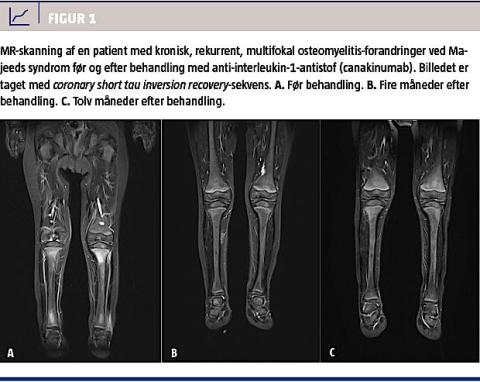

Konventionel røntgenundersøgelse kan vise osteolytiske eller osteosklerotiske læsioner, men kan i den tidlige fase vise normale forhold [9]. MR-skanning er særdeles velegnet til at afsløre de osteomyelitiske læsioner med, endda allerede på et tidligt trin, hvor der ses knogleødem, før de osteolytiske eller skleroserende forandringer opstår [9, 10]. Desuden kan man ved MR-skanning påvise associerede detaljer som periosteitis, bløddelsinflammation og ledvæskeansamling, som er fund, der ofte underestimeres ved almindelig røntgenundersøgelse. Da CNO er en systemisk sygdom, som afficerer multiple knogler, har knoglescintigrafi (99mTc-mærket methylen-difosfonat-knoglescintigrafi) været anvendt, og man har ofte fundet klinisk symptomfri læsioner. Dog kan opladning i vækstzonen hos et endnu ikke udvokset barn være svær at skelne fra metafysære forandringer set ved CRMO, hvorfor MR-skanning tit foretrækkes [11]. Helkrops-MR-skanning anvendes nu i stigende grad, både initialt i forløbet for at sikre afsløring af

ikkesymptomgivende læsioner [2, 12, 13] og som led i opfølgning af et behandlingsforløb (Figur 1). Ved knoglebiopsi finder man uspecifikke, histopatologiske forandringer med dominans af polymorfkernede leukocytter i det tidlige stadie og senere fortrinsvis plasmacelle- og lymfocytinfiltration samt evt. knogleresorption og reaktiv skleroserende knoglenydannelse [6]. Som led i diagnostikken er radiologi og biopsi vigtige redskaber til udelukkelse af differentialdiagnoser, som bl.a. malign sygdom og infektiøs osteitis.

Majeeds syndrom (Online Mendelian Inheritance in Man #609628) er en sjælden, autosomalt recessiv arvelig lidelse, hvor der hos patienterne udvikles kronisk rekurrent multifokal osteomyelitis meget tidligt (før toårsalderen). Lidelsen viser sig også ved mikrocytær kongenit dyserytropoietisk anæmi og neutrofil dermatose [23]. Syndromet er koblet til en mutation i LPIN2, som koder for lipin-2-proteinet [24]. Sygdommen har et noget sværere forløb end de fleste tilfælde af CRMO og kan være ledsaget af periodisk feber. Lipin-2-proteinet formodes at spille en rolle i lipidstofskiftet, men der savnes en forklaring på, hvilken rolle proteinet spiller i forhold til den autoinflammatoriske fænotype af Majeeds syndrom. Det er

påpeget, at mutationer i LPIN2 påvirker fosfatidinsyrefosfatidaseaktivitet af lipin-2-proteinet, hvilket reducerer dets evne til at defosforylere fosfatidinsyre til diacylglycerol [25]. Fedtsyre kan inducere et proinflammatorisk respons via signal gennem toll-like-

receptor

-aktivering og inducere aktivitet i nucleotide-binding domain leucin-rich repeat and pyrin domain containing protein 3-inflammasomet [26]. Sygdommen har tidligere været refraktær over for immunsupprimerende behandling. For nylig er det påvist, at behandling med IL-1-hæmmer har en eklatant og varig virkning ved Majeeds syndrom, hvilket tyder på, at LPIN2-mutationen er koblet til øget inflammasomaktivitet ved denne sygdom [27].